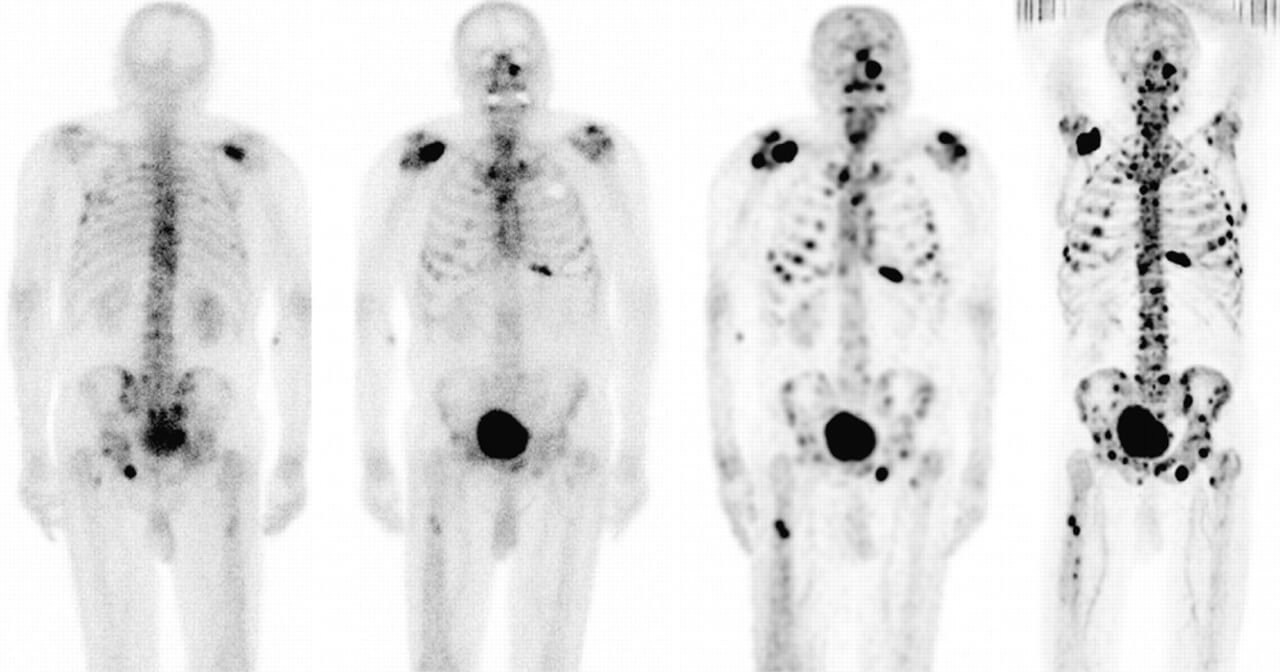

Для підтвердження діагнозу лікарі використовують різні методи дослідження, такі як рентген, комп’ютерна томографія (КТ), магнітно-резонансна томографія (МРТ) та позитронно-емісійна томографія (ПЕТ).

Метастази в кістках – це процес, коли злоякісні клітини з первинного місця походження раку поширюються в інші ділянки тіла, зокрема в кістки. Кісткові метастази є одним із найчастіших місць, куди мігрують ракові клітини, зумовлюючи больові відчуття, слабкість, підвищену ламкість кісток та навіть призводячи до інвалідності.